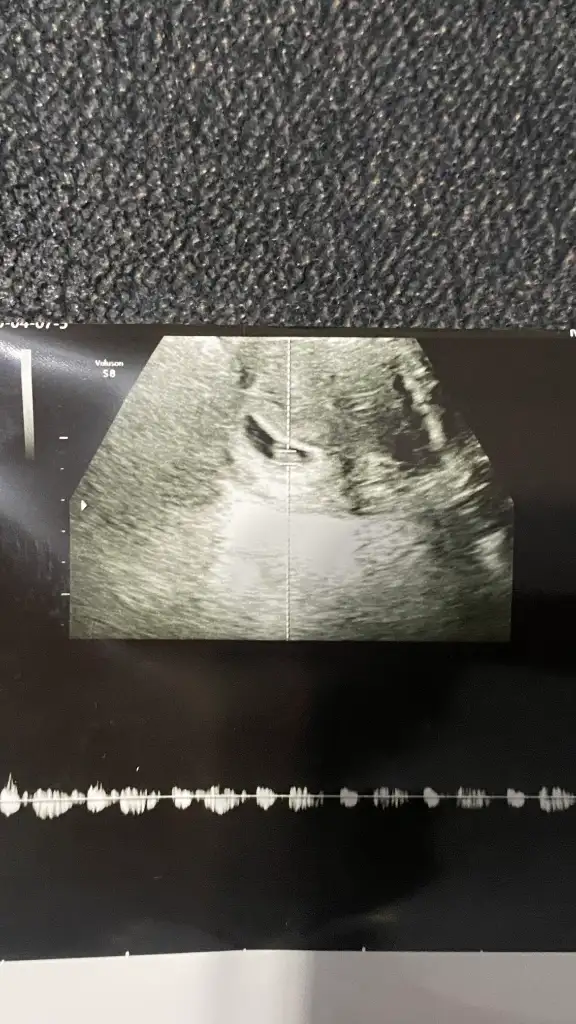

Teşekkür ederim tahmininiz için elimde 6 hafta 4 günlük ultrason görüntüsüde var bebeğimin onada bakıp tekrar tahmininizi söyler misiniz rica etsem

Eklentiler